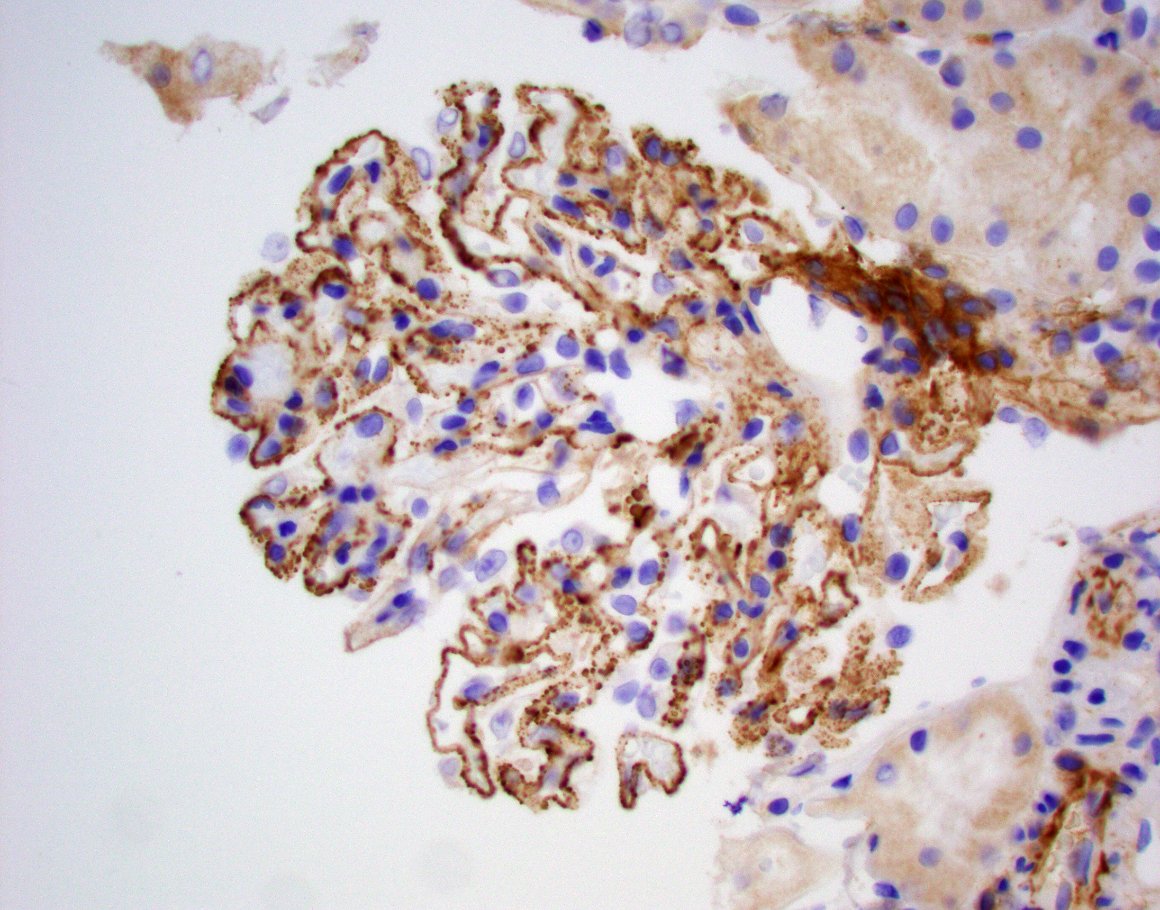

Diagnosis unmasked. Young F with 2g proteinuria, weak +dsDNA. Membranous pattern, IF with C3 dominant staining. Pronase IF --> IgG-k. Membranous-like glomerulopathy with masked monotypic IgG-k deposits. Considered to be autoimmune; not MGRS. #renalpath #pathtwitter #nephrology.

Typically occurs in young women with vague autoimmune history. Has not been associated with MGUS, plasma cell dyscrasias, or lymphomas. Deposits + for SAP. See references here: . https://t.co/CNa8qlPQkb https://t.co/qN4wxgDJp3

SAP stain is positive as well.